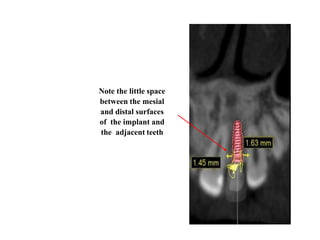

Axial cross-

section on the

root level

showing the

space around

the implant.

Note the little space

between the mesial

and distal surfaces

of the implant and

the adjacent teeth